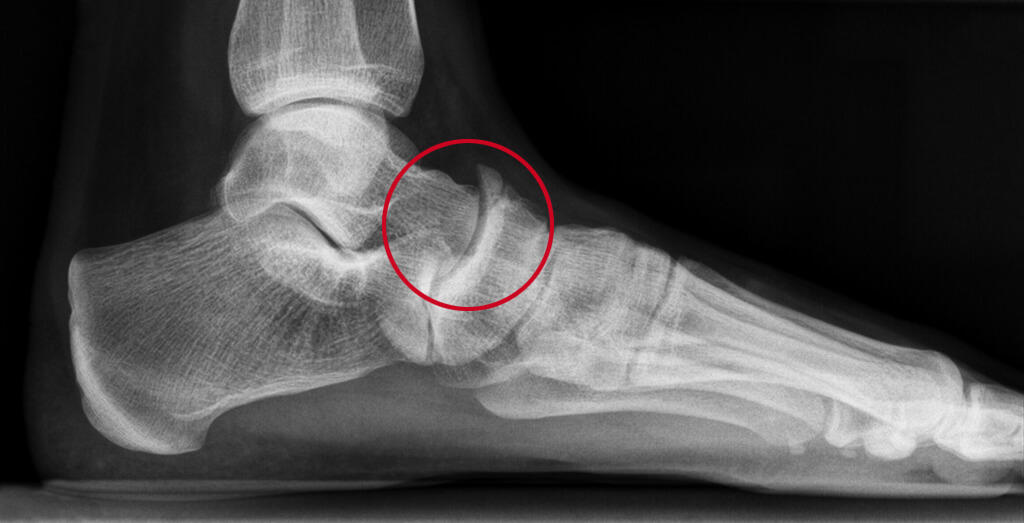

Slijtage in het talo-naviculaire gewricht

Artrose in het talo-naviculaire gewricht veroorzaakt pijn en stijfheid bij het buigen van de voet. Slijtage belemmert soepel bewegen op oneffen ondergrond.

Het talo-naviculaire gewricht is het gewricht tussen de voorkant van het sprongbeen (talus) en het zogenaamde scheepsvormig beentje (naviculare). U gebruikt dit gewricht bij het naar binnen en buiten buigen van de voorvoet, zoals bij lopen op oneffen terrein.

Bij artrose is er sprake van slijtage van het kraakbeen in het gewricht. Kraakbeen is nodig om de botten soepel langs elkaar te laten bewegen. Slijtage is normaal bij het ouder worden, maar bij artrose is de slijtage aan het kraakbeen overmatig. Het gladde oppervlak wordt dun, brokkelig of het kraakbeen verdwijnt helemaal. Hierdoor komt er steeds meer wrijving tussen de botten en dat doet pijn. Het lichaam kan de slijtage niet meer repareren.

Als de artrose erger wordt, kunnen aan de randen van het gewricht ook botuitstulpingen ontstaan, deze heten osteofyten. Die maken het bewegen extra moeilijk en pijnlijk.